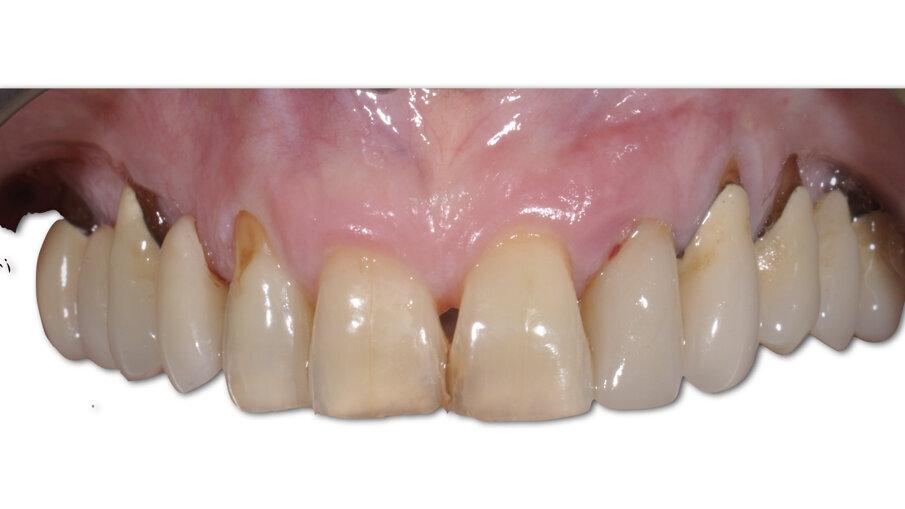

La paziente, B.G. di sesso femminile, di anni 71, è giunta alla nostra osservazione per la mobilità e lieve dolore a carico dell’elemento 2.2 (incisivo laterale superiore sinistro) (Fig. 1). All’esame ispettivo l’elemento presenta mobilità di grado 3. Al sondaggio parodontale presenta una tasca mesiale di 7 mm e di 3 mm lungo le altre superfici del dente. All’esame radiografico, eseguito con radiografia endorale periapicale, si osserva un’area di radiotrasparenza riconducibile a riassorbimento osseo soprattutto in sede mesiale (Fig. 2).

Fig. 12_Confronto tra la situazione iniziale, quella post-chirurgica e quella al termine del periodo provvisorio.